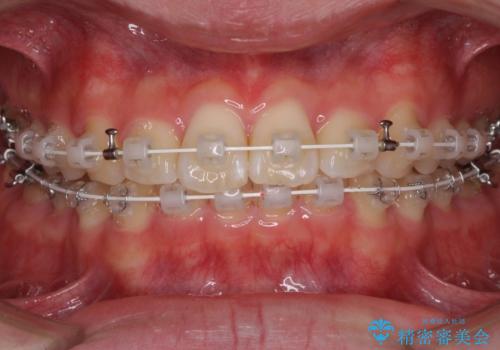

深い咬み合わせとデコボコ ワイヤー矯正で短期治療

- 審美装置

インビザラインでの治療も可能でしたが、深い咬み合わせと奥歯の咬み合わせを改善するにあたり、ワイヤー矯正の方が治療期間を短縮できると判断し、ワイヤー矯正をお勧めしました。

結果として、1年かからずに奥歯の咬み合わせを改善することができました。